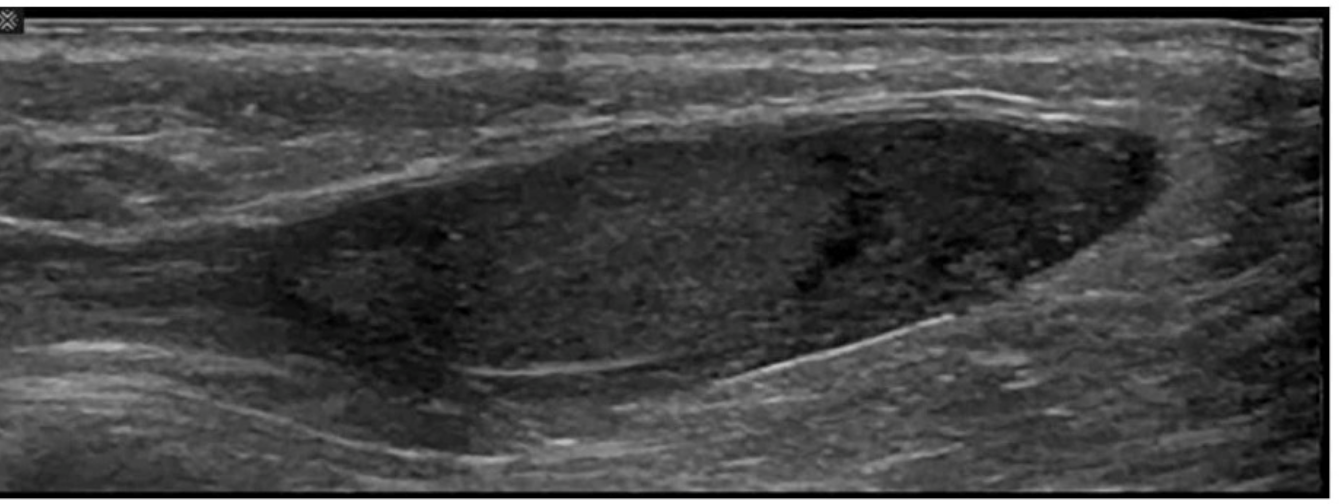

Which condition is most consistent with the sonographic appearance in this image of the abdominal wall?

Answer : A

The ultrasound image demonstrates a well-defined, ovoid, hypoechoic to isoechoic mass within the subcutaneous tissue of the abdominal wall. The lesion appears compressible and shows linear striations parallel to the skin surface --- a classic appearance of a lipoma.

Lipomas are the most common benign soft tissue tumors and frequently arise in the subcutaneous tissue. They are composed of mature adipose tissue and are typically asymptomatic unless large or compressing adjacent structures.

Isoechoic to mildly hyperechoic or hypoechoic relative to subcutaneous fat

Oval or elliptical in shape with well-defined margins

Internal linear striations or ''feathered'' echotexture

Compressible and non-vascular on Doppler imaging

Located in subcutaneous fat plane parallel to the skin surface